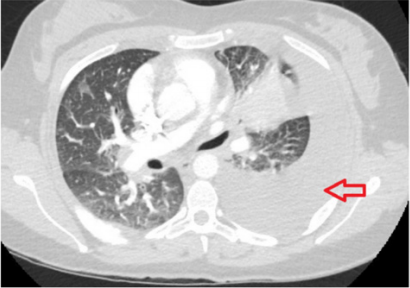

A 26-year-old female with insignificant past medical history presented to the emergency department with worsening shortness of breath following an upper respiratory tract infection for which she completed a course of azithromycin (Z-pack). A chest x-ray was done which showed abnormal parenchymal opacity at the left lower lung consistent with atelectasis and/or infiltrate, in addition to a small left effusion. A computed tomography imaging (CT scan) of the chest with intravenous (IV) contrast ruled out pulmonary embolism but showed very large left-sided pleural effusion and soft tissue density extending outward from the left hilum representing atelectasis with the possibility of an underlying mass (Figure 1). The patient had thoracentesis of her left lung and the pathological analysis of the pleural fluid showed exudates with malignant cells. Trans-abdominal ultrasound (US) to rule out Meigs syndrome showed no acute findings, however, it did show a heterogeneous lesion measuring up to 1.5 cm within the musculature of the right lower abdominal wall which corresponded to the palpable abnormality on her physical examination. US ascites survey showed no abdominal ascites. US pelvis showed 1.5 cm intramuscular lesion. CT of the abdomen and pelvis showed no acute process but a subtle 1.8 cm hypodense lesion in the right hepatic lobe that is indeterminant. Flexible bronchoscopy with bronchoalveolar lavage and biopsies was performed.

Figure 1: A computed tomography imaging of the chest with intravenous contrast showing very large left-sided pleural effusion and soft tissue density extending outward from the left hilum with the possibility of an underlying mass.